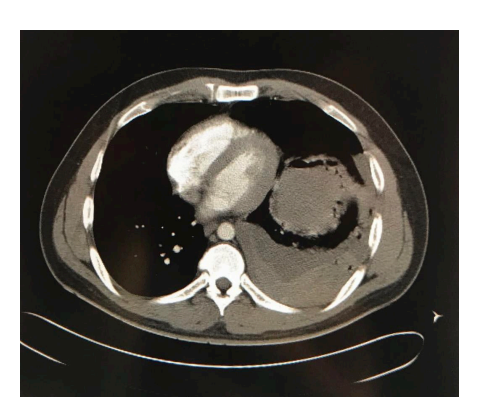

A 33-year-old immunocompetent man brought to the emergency room with symptoms of dry cough, chest pain, and dyspnea for several days and hemoptysis of five days of evolution. His clinical history revealed that he had suffered from pulmonary aspergillosis a month ago without any history of trauma and received treatment with antifungal drug voriconazole for 2 weeks; however, he had poor outpatient follow up of antifungal treatment. His vital signs on admission were as follows: blood pressure 90/50 mmHg, heart rate 114 beats/min, respiratory rate: 18 breaths/min, body temperature 36.3 °C, bodyweight: 190 lbs., height: 5’10’’, and body-mass index 27.2 kg/m2. His physical examination was remarkable for decreased breath sounds on the left hemithorax, otherwise normal examination. Chest radiograph showed a left-sided apical pneumothorax associated with pleural effusion, right mediastinal shifting, and cavitary lesion (Figure 1). Computed tomography (CT) scan of the chest confirmed the presence of a thick-walled cavitary lesion with bronchopleural fistula (Figure 2). Additionally, a complex hemorrhagic left-sided hemopneumothorax linked with the collapse of left lung was detected (Figure 3).

Laboratory evaluation of complete blood count (CBC) showed significant leukocytosis (25,700) with stable hemoglobin level (12.1mg/dL) and platelet count (Table 1). Complete metabolic panel (CMP) data was consistent with hyperglycemia with blood glucose level of 236 and acute kidney injury with a creatinine level of 1.49, lactic acid of 43.7 mg/dL, and coagulation profile within normal range (Table 1). The basal metabolic panel (BMP) showed sodium 139, potassium 4.2, chloride 106, and bicarbonate 23 (Table 1). Arterial blood gas (ABG’s) measures indicated partial pressures of carbon dioxide (pCO2) and oxygen (pO2) to be 32.8 mmHg and 75.1 mmHg respectively and oxygen saturation of 95.2% (Table 1). The patient was subjected to emergency left-sided thoracostomy and about 1,400mL of bright red blood was drained from the thoracostomy tube. Subsequently, he became hemodynamically unstable, with a decrease in hemoglobin from 12.1 mg/dL to 9 mg/dL. Intravenous antifungal and antibiotic therapy (Voriconazole and Vancomycin + Meropenem) were started immediately based on patient critically ill state and established by Infectious disease specialist to provide adequate broad spectrum antimicrobial coverage for fungal, MRSA and anaerobic species. Due to continued drainage and hemodynamic instability a left lower lobectomy of the lung was performed by cardiothoracic surgeon. The patient responded to the treatment well and ultimately his clinical symptoms were subsided within 1 week.